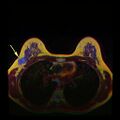

يشير فحص سرطان الثدي إلى اختبار النساء اللائي يتمتعن بصحة جيدة لسرطان الثدي في محاولة لتحقيق تشخيص مبكر على افتراض أن الاكتشاف المبكر سيحسن النتائج. تم استخدام عدد من اختبارات الفحص بما في ذلك الفحص السريري والذاتي فحوصات الثدي وتصوير الثدي والفحص الجيني والموجات فوق الصوتية والتصوير بالرنين المغناطيسي.

ينص تعاون كوكرين (2013) على أن أفضل دليل جودة لا يوضح انخفاضًا في سرطان محدد، ولا انخفاض في جميع أسباب الوفيات الناتجة عن فحص التصوير الشعاعي للثدي.[9] عند إضافة تجارب أقل صرامة إلى التحليل، يحدث انخفاض في معدل الوفيات بسبب سرطان الثدي بنسبة 0.05% (انخفاض 1 كل 2000 حالة وفاة بسبب سرطان الثدي على مدى 10 سنوات أو انخفاض نسبي بنسبة 15% للوفيات بسبب سرطان الثدي).[9] يؤدي الفحص على مدى 10 سنوات إلى زيادة بنسبة 30% في معدلات الإفراط في التشخيص والعلاج الزائد (3 إلى 14 لكل 1000) وأكثر من نصفهم سيحصلون على اختبار واحد إيجابي كاذب على الأقل.[9][118] وقد أدى ذلك إلى الرأي القائل بأنه ليس من الواضح ما إذا كان فحص التصوير الإشعاعي للثدي يفيد أم يضر أكثر.[9] بحسب كوكرين أنه بسبب التحسينات الأخيرة في علاج سرطان الثدي، ومخاطر الإيجابيات الكاذبة من فحص سرطان الثدي التي تؤدي إلى علاج غير ضروري، "لذلك لم يعد من المفيد الحضور لفحص سرطان الثدي" في أي عمر.[119] ليس معروفًا ما إذا كان التصوير بالرنين المغناطيسي كطريقة فحص له أضرار أو فوائد أكبر مقارنةً بالتصوير الإشعاعي للثدي القياسي.[120][121]

- حيثما كان ذلك متاحًا، يمكن استخدام دراسات التصوير كجزء من عملية التدريج في حالات مختارة للبحث عن علامات السرطان النقيلي. ومع ذلك، في حالات سرطان الثدي مع انخفاض خطر الإصابة بورم خبيث، فإن المخاطر المرتبطة بالتصوير المقطعي بالإصدار البوزيتروني، التصوير المقطعي المحوسب، أو مسح العظام تفوق الفوائد المحتملة، لأن هذه الإجراءات تعرض الشخص لكمية كبيرة من الإشعاع المؤين الذي يحتمل أن يكون خطيرًا.[126][127]